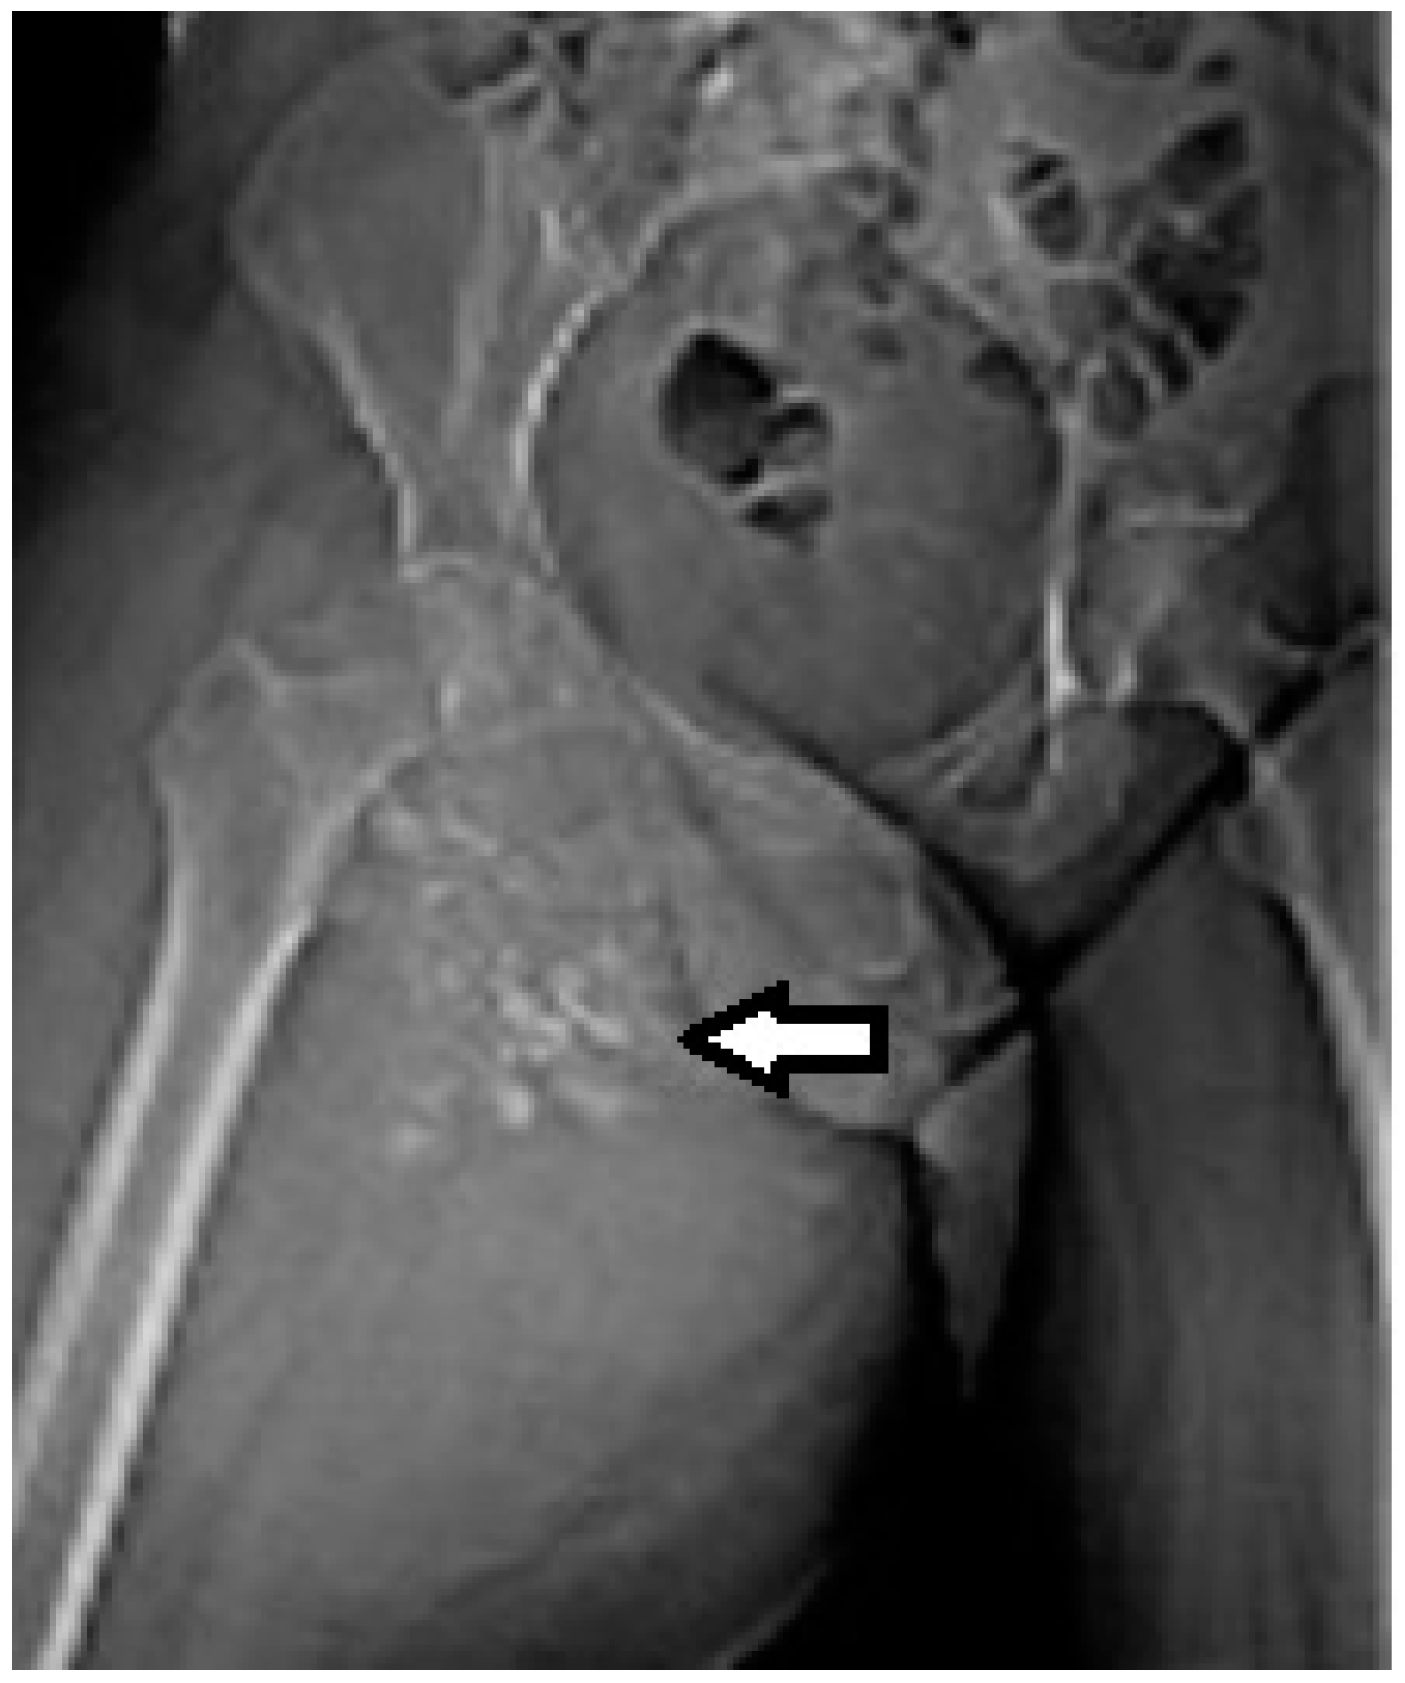

2.2. Imaging Examinations